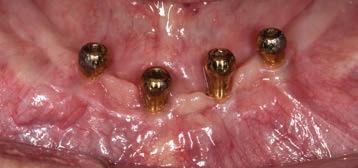

Keratinized tissue around implants

Compared to natural teeth, the soft tissue around dental implants provides less of an anatomical barrier as it does not have inserting fibers attaching to the implant or abutment.2-4 An implant has a transmucosal component (an abutment, neck of the implant, or implant restoration) that protrudes through the overlying mucosa/

gingiva, which heals and adapts around it without an inserting connective tissue attachment such as around teeth. Although some studies showed circular fibers present around the transmucosal part of implants4, it is well-known that the barrier function of the peri-implant tissue is less effective than that of natural teeth. The importance of having sufficient keratinized tissue around dental implants has been emphasized in recent studies.2-5 Mobile alveolar mucosa is not able to provide an adequate seal between the oral environment and the implant body. In patients with inadequate plaque control, this may become even more crucial, as inflammation may distend the mucosa more readily and render the area more uncomfortable to oral hygiene efforts. This in turn may lead to more bone loss around the neck of the implant.2, 4, 6, 7

A reduced width of keratinized tissue around dental implants is associated with increased biofilm accumulation, soft-tissue inflammation, greater patient discomfort, mucosal recession, marginal bone loss and an increased prevalence of peri-implantitis.4, 7 Free gingival autogenous grafts are considered the standard of care for surgical intervention to effectively increase the width of keratinized tissue around dental implants. The presence of a minimum width of at least

2-3mm of keratinized tissue around dental implants should therefore be assessed routinely in patients with implant supported restorations. 7 It should, however, be stressed that the keratinized tissue should have an attached component to protect the coronal bone around the implant to provide an effective seal. In recent studies the importance of adequate thickness of the keratinized tissue has also been emphasized.3

Epithelial palatal transplant (EPT) to increase the width and thickness of keratinized tissue around implants

Grafting of soft tissue can be done at three different time periods: before implant placement (Figs 4a-c), at the same time (Figs 5a-c) or after implant placement (Figs 6a-c). Experienced clinicians may opt to perform an EPT simultaneously with implant placement as this saves multiple surgical procedures and is more cost effective. This is shown in Fig 5 and also in the video link provided. This is a complex procedure which should not be attempted by inexperienced clinicians. Grafting before the implant placement is the more predictable procedure and provides a better implant environment to place the implant.

Figure 4a: Pre-operative view showing alveolar mucosa almost to crest of ridge Figure 4b: Graft secured with vestibular deepening done as well Figure 4c: Post-operative view showing graft healing after 8 weeks

Figure 5a: Preoperative view with mucogingival line shown in blue Figure 5b: Simultaneous implant placement and epithelial palatal transplant Figure 5c: Postoperative view with crowns placed. Rugae can be seen but, as it is not an aesthetic area, this is of no consequence Figure 6a: Implants placed years before with peri-implantitis and no keratinized attached tissue buccal of implants. Figure 6b: Graft providing keratinized tissue as well as vestibuloplasty. Patient can wear prosthesis but it has to be eased to ensure no pressure on graft Figure 6c: Postoperative view showing a stable attached peri-implant keratinized tissue and vestibular deepening giving better access for plaque control